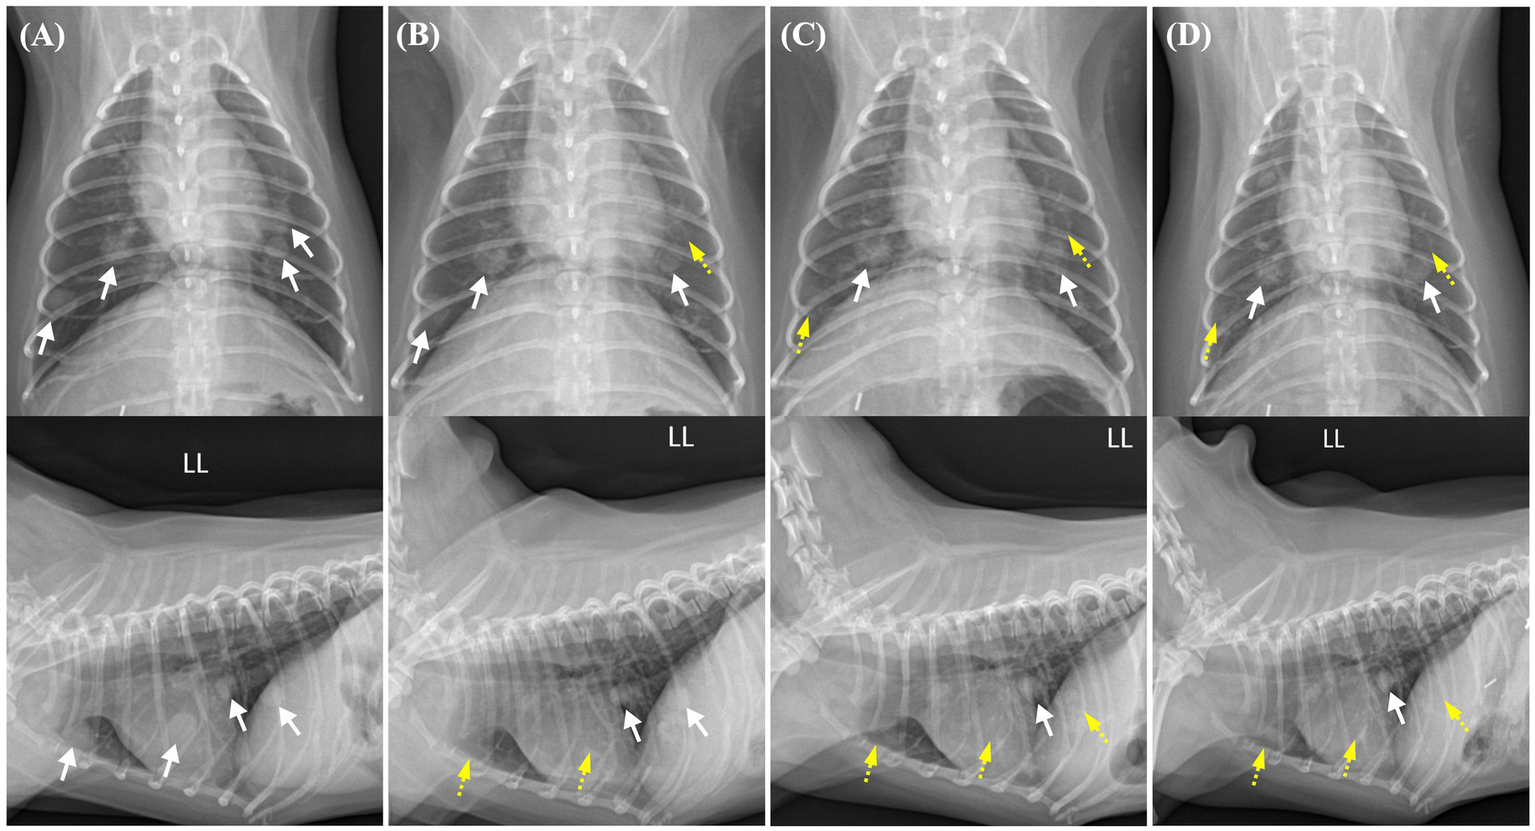

Changes in the pulmonary nodules on thoracic radiographs from before toceranib administration to 2 weeks, 2 months, and 4 months after treatment initiation. Pulmonary nodules with well-defined borders are indicated by white arrows, whereas regressed nodules are indicated by yellow dashed arrows. (A) Prior to toceranib administration, multiple pulmonary nodules with soft tissue opacity are observed throughout the generalized lung field. The pulmonary nodule with the largest size measures 11.4 × 8.8 mm. (B) In a thoracic radiograph obtained 2 weeks after toceranib administration, the previously identified pulmonary nodule with the largest size is no longer visible in the lateral view. The largest measurable diameter of the remaining nodule is approximately 9 mm. (C) In a thoracic radiograph obtained 2 months after toceranib administration, another pulmonary nodule initially sized 8.4 × 7.7 mm is no longer detected. The majority of the pulmonary nodules exhibit partial remission and a diminished size. (D) In a thoracic radiograph obtained 4 months after toceranib administration, no further remission is observed in the existing pulmonary nodules. Indications of newly detected nodules or the recurrence of previously diminished pulmonary nodules are also not found.

Thus, 1 month after the surgery, toceranib administration was initiated at 2.27 mg/kg orally every 48 h, in accordance with the label’s minimum dosage recommendation. The dose was adjusted with consideration for possible adverse effects and potential future dose escalation. The medical recheck intervals for adverse drug events, tumor recurrence, and metastasis were once per week for the first 2 weeks, followed by every 2 weeks for 4 weeks and monthly thereafter. At the 2-week follow-up examination, no adverse effects were observed following assessments of systemic blood pressure measurement, CBC, serum chemistry profile, coagulation profile, and urinalysis, based on the veterinary cooperative oncology group-common terminology criteria for adverse events (VCOG-CTCAE) criteria (12). Serial changes in the pulmonary nodules following the administration of toceranib are shown in Figure 2. Pulmonary nodules, suspected to be metastases of renal cell carcinoma, exhibited a decrease in size and opacity on thoracic radiography, accompanied by blurring of their borders (Figure 2B). The owner reported that the dog was active and exhibited normal eating, drinking, urination, and stable breathing.

At the 2-month check-up, the patient was observed to have consistently maintained a good condition. The owner reported that the patient appeared to be pain-free, displaying high energy levels and a strong appetite. No remarkable findings were observed concerning the tumors or adverse effects of toceranib. On thoracic radiography, most of the pulmonary nodules exhibited partial remission and had diminished in size (Figure 2C). Abdominal ultrasonography revealed no additional findings suggestive of RCC metastasis.

At the 4-month check-up, in comparison to the thoracic radiograph from 2 months ago, there was no further regression observed in the existing pulmonary nodules; they appeared similar. Nevertheless, there were no signs of recurrence in those that had previously shown remission, and no additional nodules were detected (Figure 2D). Similarly, no adverse effects related to chemotherapy were observed according to the VCOG-CTCAE criteria (12). However, 1 week before the scheduled 5-month check-up, the patient experienced severe fatigue, vomiting, and diarrhea and died at home without a definitive cause. This occurred 6 months after the initial detection of the renal mass and subsequent surgery and 5 months after the administration of toceranib. A necropsy was not performed because of the owner’s refusal.